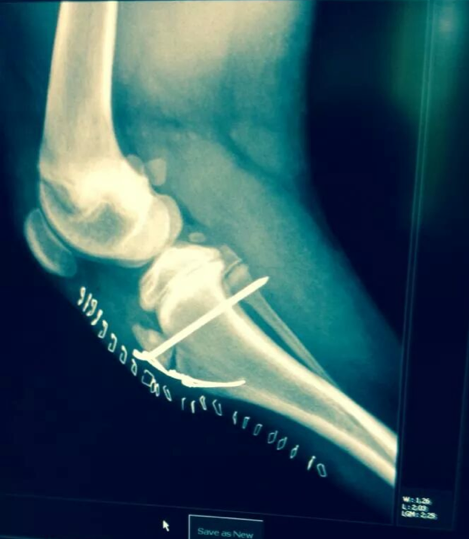

Please look below at all these x-rays from last years random friend’s injuries ( and these are without even searching as these happen all the time). If it is not a growth plate , it is a neck, back, wrist, hock, ribs or any large bones for that matter. One of the most common example is when a small piece of the knee joint splits, which end up in a 2-3000€ surgery. I do not see much point in taking such a huge risk, so don’t run adults and pups! Period!

Here is the proof! More info after the pictures!

Surgery • Surgery is generally done as soon as possible after this type of injury occurs.

• Generally pins are used to repair these types of fractures if a type 1 or 2 fracture occurs.

• Type 3 and 4 may need a screw and pin placed. If the joint surface has been directly violated as in a type 3 or 4 fracture the joint should only be immobilized with a bandage or splint/cast for a very short period of time. Prolonged splinting of a limb that has had a repaired joint fracture could lead to permanent stiffness of the joint.

• The elbow and knee seem to be the most common regions to have problems if immobilized for too long (get scar tissue and joint becomes very stiff).